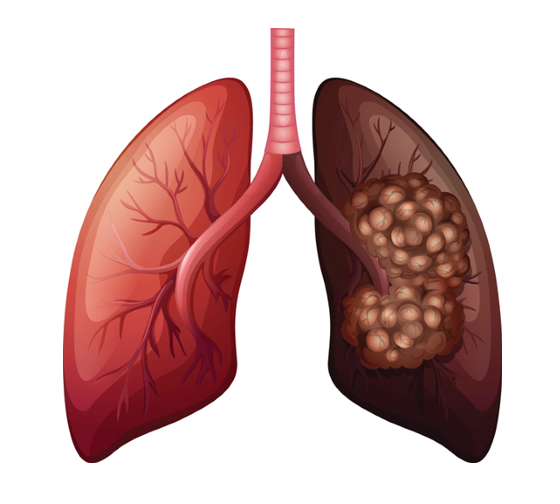

폐암은 국내 암 사망률 1위로, 과거에는 흡연이 폐암의 주요 원인이었지만 최근에는 비흡연자의 폐암 발병이 크게 증가하고 있습니다. 폐암은 오랜 기간 암 사망률 1위를 차지하고 있지만, 의학의 발전으로 생존율이 높아지고 있습니다. 그러나 초기 단계에서 올바르게 관리하는 것이 중요합니다. 폐암의 초기 징후가 무엇인지, 폐암에 좋은 음식은 무엇인지 알아두는 것이 좋습니다.

흡연자와 비흡연자를 비교하면 흡연자는 폐암에 걸릴 확률이 낮게는 15배, 높게는 80배까지 높아질 수 있고, 폐암의 마지막 원인 중 하나이기 때문에 흡연자라면 금연을 하는 것이 정말 좋습니다.